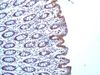

| Applications | IHC |

| Reactivities | Human |

| Conjugation | Unconjugated |

| Immunogen | The antiserum was produced against synthesized peptide derived from human Caspase 1. |

| Immunogen | CASP1 antibody was raised against a synthetic peptide from the second quarter of human Caspase 1 protein |